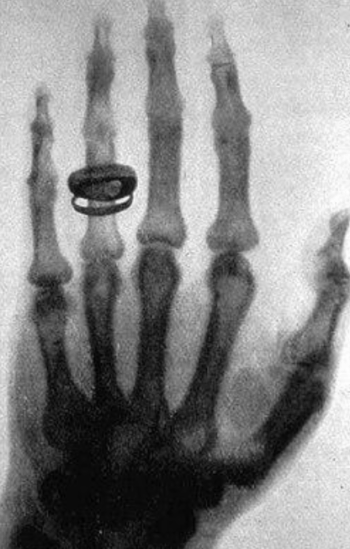

Συνοδεύεται και ενισχύεται από πληθώρα τεχνολογικών εξελίξεων, που είναι εντυπωσιακές αν θυμηθούμε την εποχή που ο κύριος Röntgen απεικόνισε την παλάμη της συζύγου του, με τη βοήθεια των «αόρατων» ακτίνων Χ, 130 χρόνια πριν στις 8/11/1895. Όλα αυτά τα χρόνια, έχουν σημειωθεί άλματα στη δυνατότητα της απεικόνισης πολλαπλών σημείων και συστημάτων του οργανισμού, σε όλες τις ηλικίες με λεπτομέρειες που συχνά θυμίζουν ανατομικό ή χειρουργικό παρασκεύασμα. Με αυτόν τον τρόπο, η Ακτινολογία έχει βοηθήσει στη διάγνωση πολλαπλών παθήσεων, συχνά σε πρώιμο στάδιο και έχει συνεισφέρει ουσιαστικά στην αποτελεσματικότερη θεραπεία και παρακολούθηση πολλαπλών ασθενειών, δίνοντας ώθηση στην πρόοδο και την εξέλιξη της Ιατρικής.